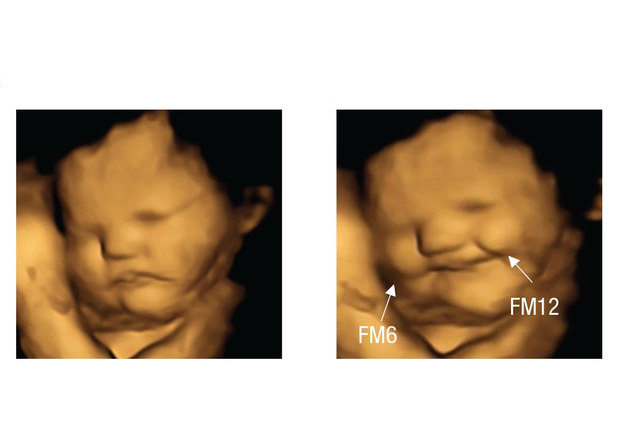

Жаклин Биссет (Jacqueline Blissett) из Астонского университета вместе с коллегами решила узнать, могут ли дети реагировать на разные продукты уже в утробе. Женщинам на 32 и 34 неделе беременности давали капсулы с морковным или капустным порошком. Сами испытуемые не знали, что внутри, а значит их личные предпочтения не могли повлиять на ход эксперимента (но они могли догадаться о содержимом по цвету капсул). Через 25 минут реакцию плода отсматривали на УЗИ с визуализацией лица. Ученые определяли эмоцию по мимике: опущенные брови и приоткрытый рот считались признаком недовольства, а приподнятые брови и щечки расценивались как положительная эмоция. Вообще ученые отследили много параметров мимики, но все они объединялись либо в «плачущее», либо в «смеющееся» лицо.

Оказалось, что человек еще до рождения действительно может реагировать на пищу. Если беременная женщина съедала капсулу с морковью, у плода чаще регистрировали мимику, характерную для «смеющегося» лица. А вот капуста, напротив, им не нравилась — «плачущее» лицо в таком случае встречалось в два раза чаще, чем при поедании моркови или состояния покоя.